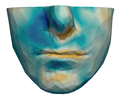

- Chin. Overall, the amount of error at the chin area is very low. This could be explained by the fact that the skin at the chin is very thin, and the coupling to the mandible makes the simulation highly predictive.

- Lips. In other regions, such as the lips, skin slides strongly over the underlying bones and teeth, and the deformation result is more difficult to predict. Overall, we observe higher variability in the error at the lips, and also some patients with higher error.

- Nose. The quality of the prediction of the deformation of the nose varies strongly across patients. In this case, the variability may depend on the type of surgery performed on each patient’s anterior nasal spine. This type of surgery is not easy to identify in the post-operative CBCT image due to the presence of bone grafts or fixation plates.

- Neck. Finally, we observe large error in the neck area (e.g., patients M5 and M8), and specifically at the junction point between the submental area and the neck (“C point” or “cervical point” in cephalometric analysis). This error was accounted for in our quantitative analysis, which negatively biased the overall results. However, this area is not of special interest to orthognathic surgeons. The deformation is known to be produced by a retraction of skin after surgery, but surgeons do not account for this effect during pre-operative planning.

| M1 |  |  |  |  |  |  |

| M2 |  |  |  |  |  | |

| M3 |  |  |  |  |  | |

| M4 |  |  |  |  |  | |

| M5 |  |  |  |  |  |

| M6 |  |  |  |  |  |  |

| M7 |  |  |  |  |  | |

| M8 |  |  |  |  |  | |

| M9 |  |  |  |  |  | |

| M10 |  |  |  |  |  |